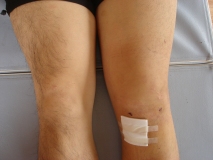

下の写真はその時の状態。絆創膏の部分および膝蓋骨下側にある二箇所の点が皮切箇所。